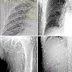

un homme chinois a vu son médecin à cause des maux d’estomac et des démangeaisons de la peau après avoir manger de sashimi (des tranches de poisson crus) les résultats étaient choquants, son corps a été entièrement infecté par les vers et les parasites suite au plat de sashimi qu’il a mangé.